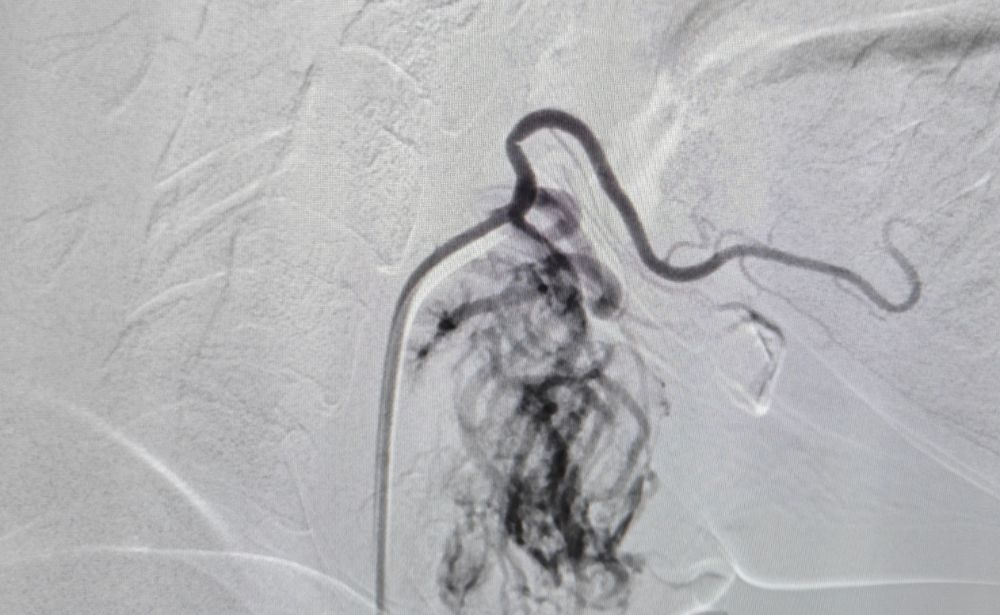

3. Embolization of Arterio-Venous Malformations (AVMs)

• The Problem: AVMs are abnormal, tangled connections between arteries and veins that can occur anywhere in the body. They can cause pain, bleeding, heart strain, and cosmetic issues.

• Our Solution: We deliver a specialized glue or embolic agent directly into the core of the AVM through a microcatheter, permanently blocking the abnormal connections.

• Patient Benefit: Can cure or significantly control AVMs, relieving symptoms and preventing serious complications like rupture or hemorrhage, all while preserving surrounding healthy tissues.